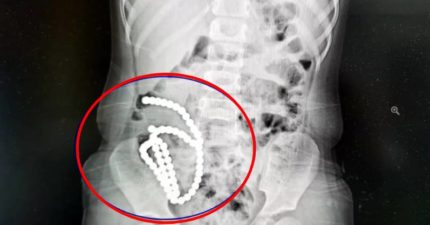

4歲妹照X光驚見「肚子整串白珠珠」 媽證實哥哥在玩!醫嘆:一輩子毀了